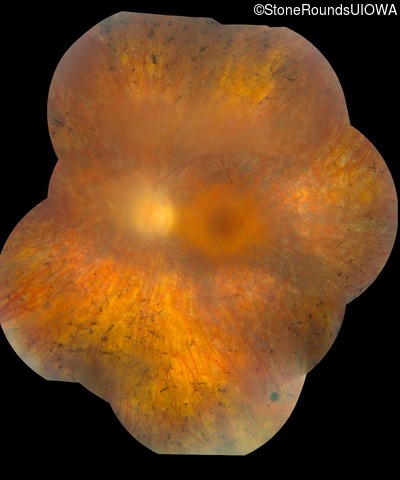

Fundus Montage - Right - 20/80 +2

Exemplar